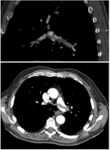

Large saddle embolus seen in the pulmonary artery (white arrows).

التكهن يعتمد على عاملين الأول على السبب والأمراض الكامنة, والثاني على سرعة التشخيص والعلاج المناسب. حوالي 10٪ من المرضى الذين يصابون بالانسداد الرئوي يموتون في غضون الساعة الأولى من حدوث الحالة, وحوالي 30٪ تموت بعد ذلك بسبب انْصِمام راجِع أو متكرر, ويمكن تقسيم وفيات الانسداد الرئوي الحاد إلى تصنيفين أو نوعين: الانسداد الرئوي الجسيم والانسداد الرئوي المحدود , وفيات لمرضى الانسداد الرئوي الجسيم عادة تتراوح بين 30٪ و 60٪، وغالبية الوفيات تحدث في الساعات الأولى من التشخيص والعلاج. أما الانسداد الرئوي المحدود وهو الأكثر شيوعا فمعدل الوفيات يكون عادة أقل من 5٪ في غضون الستة أشهر الأولى من العلاج المضاد للتخثر. ومعدل الجلطات الدموية الراجعة أو المتكررة أقل من 5٪ خلال هذه الفترة. مع ذلك، تصل إلى 30٪ بعد 10 سنوات الإصابة الأولى.